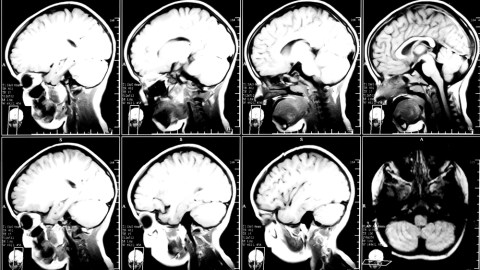

Image courtesy of Shutterstock.